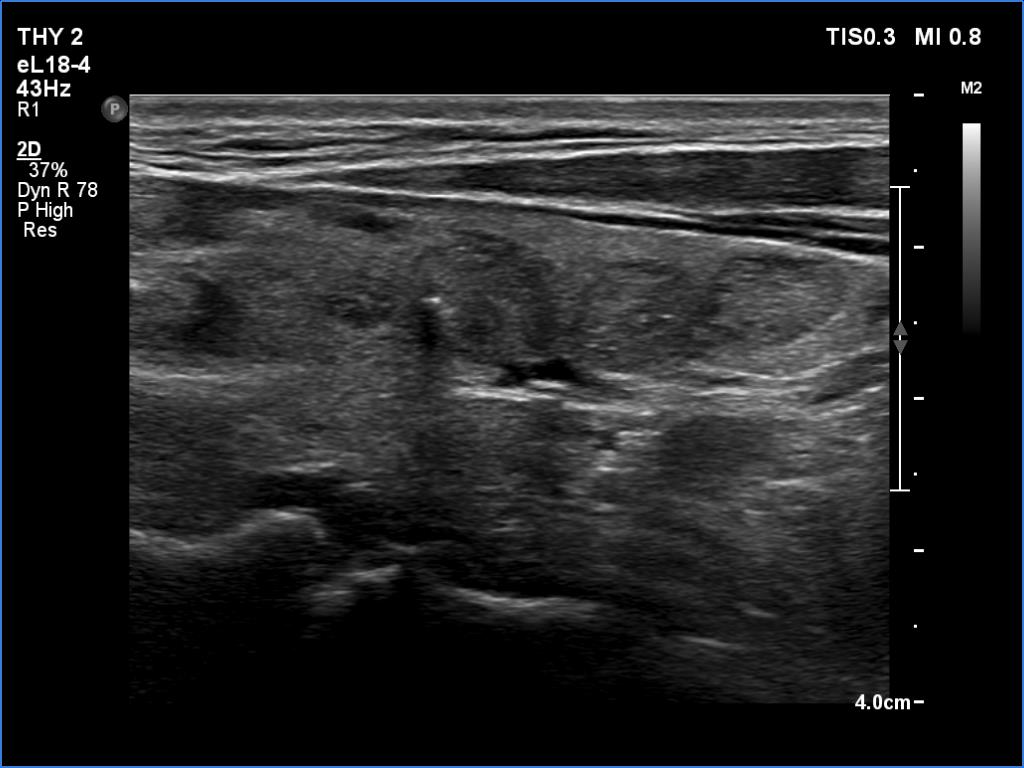

Ultrasonography. The thyroid was echonormal and had multiple minimally/moderately hypoechoic nodules. The lesion in the left lobe was remarkable due to lobulated margins. More than 10 lymph nodes larger than 1 cm in diameter were detected both in the right and the left side of the neck. Some had heterogenous pattern, most of them lacked regular hilum. The vascularity was varied from avascular to obviously irregular.